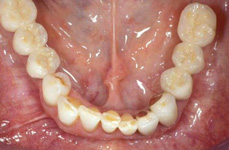

V případě chybění většího počtu zubů v postranních úsecích čelistí je možné ošetření pomocí implantátů, které nahradí ošetření pomocí snímacích náhrad kotvených na zbývajících zubech nebo patře.

Protetické řešení může být pomocí můstku, který je kotvený na implantátech nebo pomocí jednotlivých korunek na implantátech.

V zásadě je možné do těchto můstků zařadit i přirozené zuby, zejména pokud je potřeba tyto zuby ošetřit proteticky

- korunkami. Korunky nebo můstky mohou být na implantáty nacementovány nebo přišroubovány.

Zdravé zuby zůstanou zachovány a přitom náhrady jsou pevné, jako na vlastních zubech